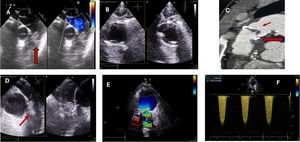

La figura 1 muestra distintas imágenes ecocardiográficas de endocarditis pulmonar.

Imágenes de endocarditis pulmonar. A)Imagen de ETE de endocarditis pulmonar nativa en paciente en UCI. Vegetación de gran tamaño en planos valvular pulmonar en plano medioesofágico alto de grandes vasos. B,C)Endocarditis protésica pulmonar. Imagen de ETT sin vegetaciones (B). TAC con engrosamiento de velos protésicos y absceso perianular (flechas). D-F)Imágenes de paciente con vegetaciones y trombo en prótesis pulmonar biológica percutánea (Melody) (ETE flechas [D]). Turbulencia en flujo transvalvular pulmonar y gradientes elevados (E,F).